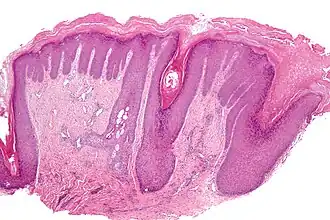

![]() Micrografía mostrando hiperqueratosis. Tinción hematoxilina-eosina. | ||

La hiperqueratosis es un trastorno caracterizado por el engrosamiento de la capa externa de la piel, que está compuesta de queratina, una fuerte proteína protectora.[1] Puede ser causado por fricción, conllevando la aparición de callos, callosidades, inflamación crónica, eccema o trastornos genéticos como la ictiosis ligada al cromosoma X o ictiosis (piel extremadamente seca)[2] y la poroqueratosis.